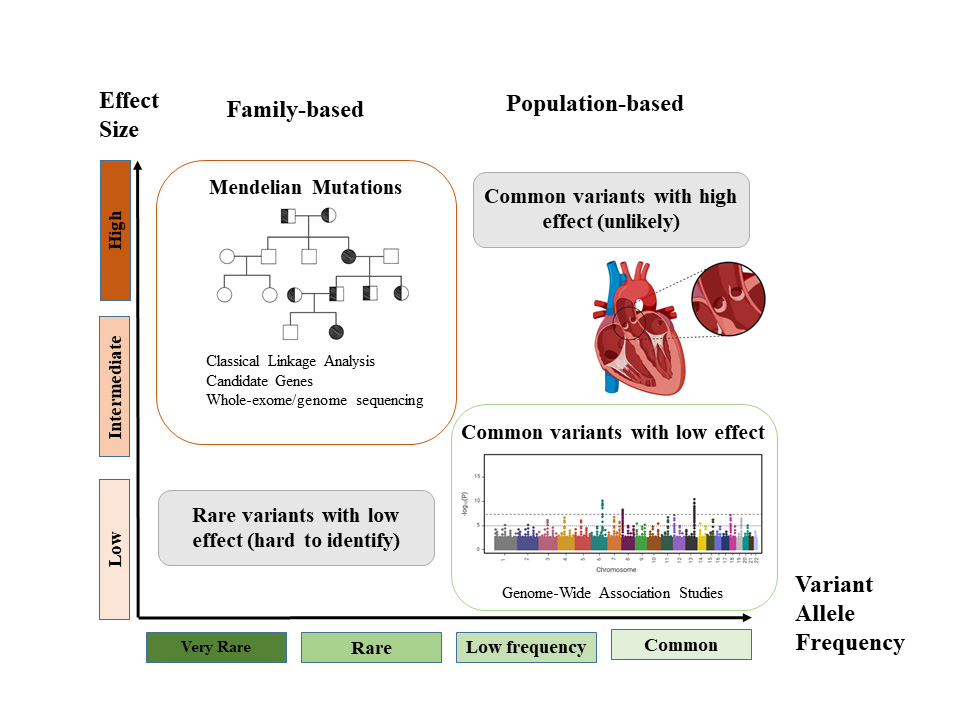

Traditionally, large families with well-documented histories have been crucial in determining the genetic basis of diseases thought genome-wide linkage analysis. However, with the advent of high-throughput technologies such as whole-exome and whole genome sequencing, as well as array comparative genome hybridization, the identification of new loci, associated genes, and chromosomal rearrangement has been accelerated. In vivo and in vitro functional studies have been decisive in dissecting molecular pathways. Nevertheless, the genetic research into valvulopathies is complicated by factors such as incomplete penetrance, phenotypic heterogeneity, and possible modifier factors which can obscure the genetic landscape of these diseases (Fig. 1).

Fig. 1.

Fig. 1.Genetic variants and human diseases. Variants with a high effect size are normally very rare and follow a Mendelian pattern of inheritance. In contrast, common variants in the general population have lower effects in the disease. Rare variants with low effect or common variants with high effect do not occur frequently.